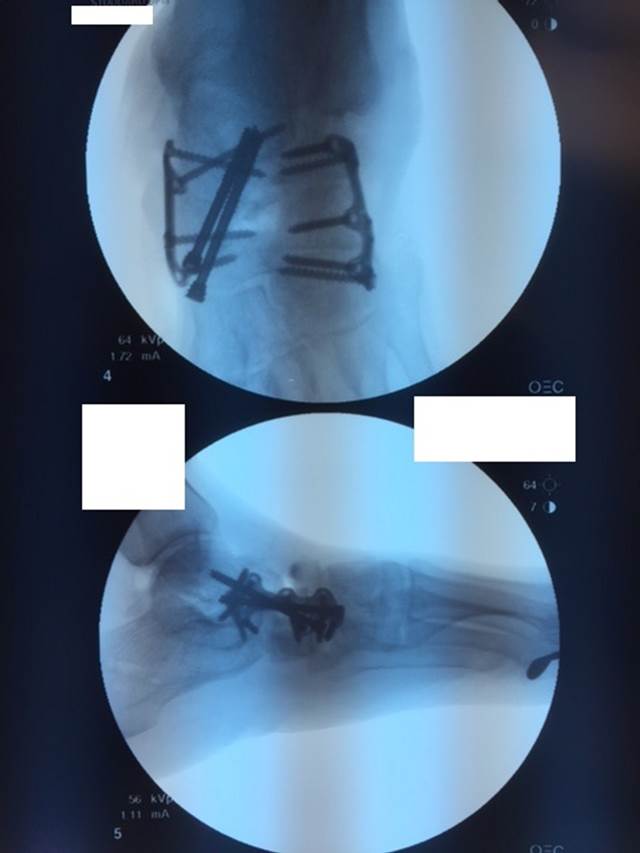

"Surgical misadventure" by another surgeon about 8 years ago. The wrong fixation was used for a flatfoot repair, & the deformity was not corrected. Patient came in with severe foot & ankle pain, with no arch at all. She was unable to play with her grandchild because the pain was so bad, & because she felt unsteady. The old hardware was removed, a lateral calcaneal lengthening osteotomy was performed along with a medial column/1st ray realignment. The ankle was painfully arthritic, & patient elected a total ankle replacement vs. an ankle fusion. She is now able to walk pain free & play with her grandchildren!

Ten years of severe ankle pain with a mal-positioned ankle fusion is now relieved! Patient is now walking with pain-free ankle motion!